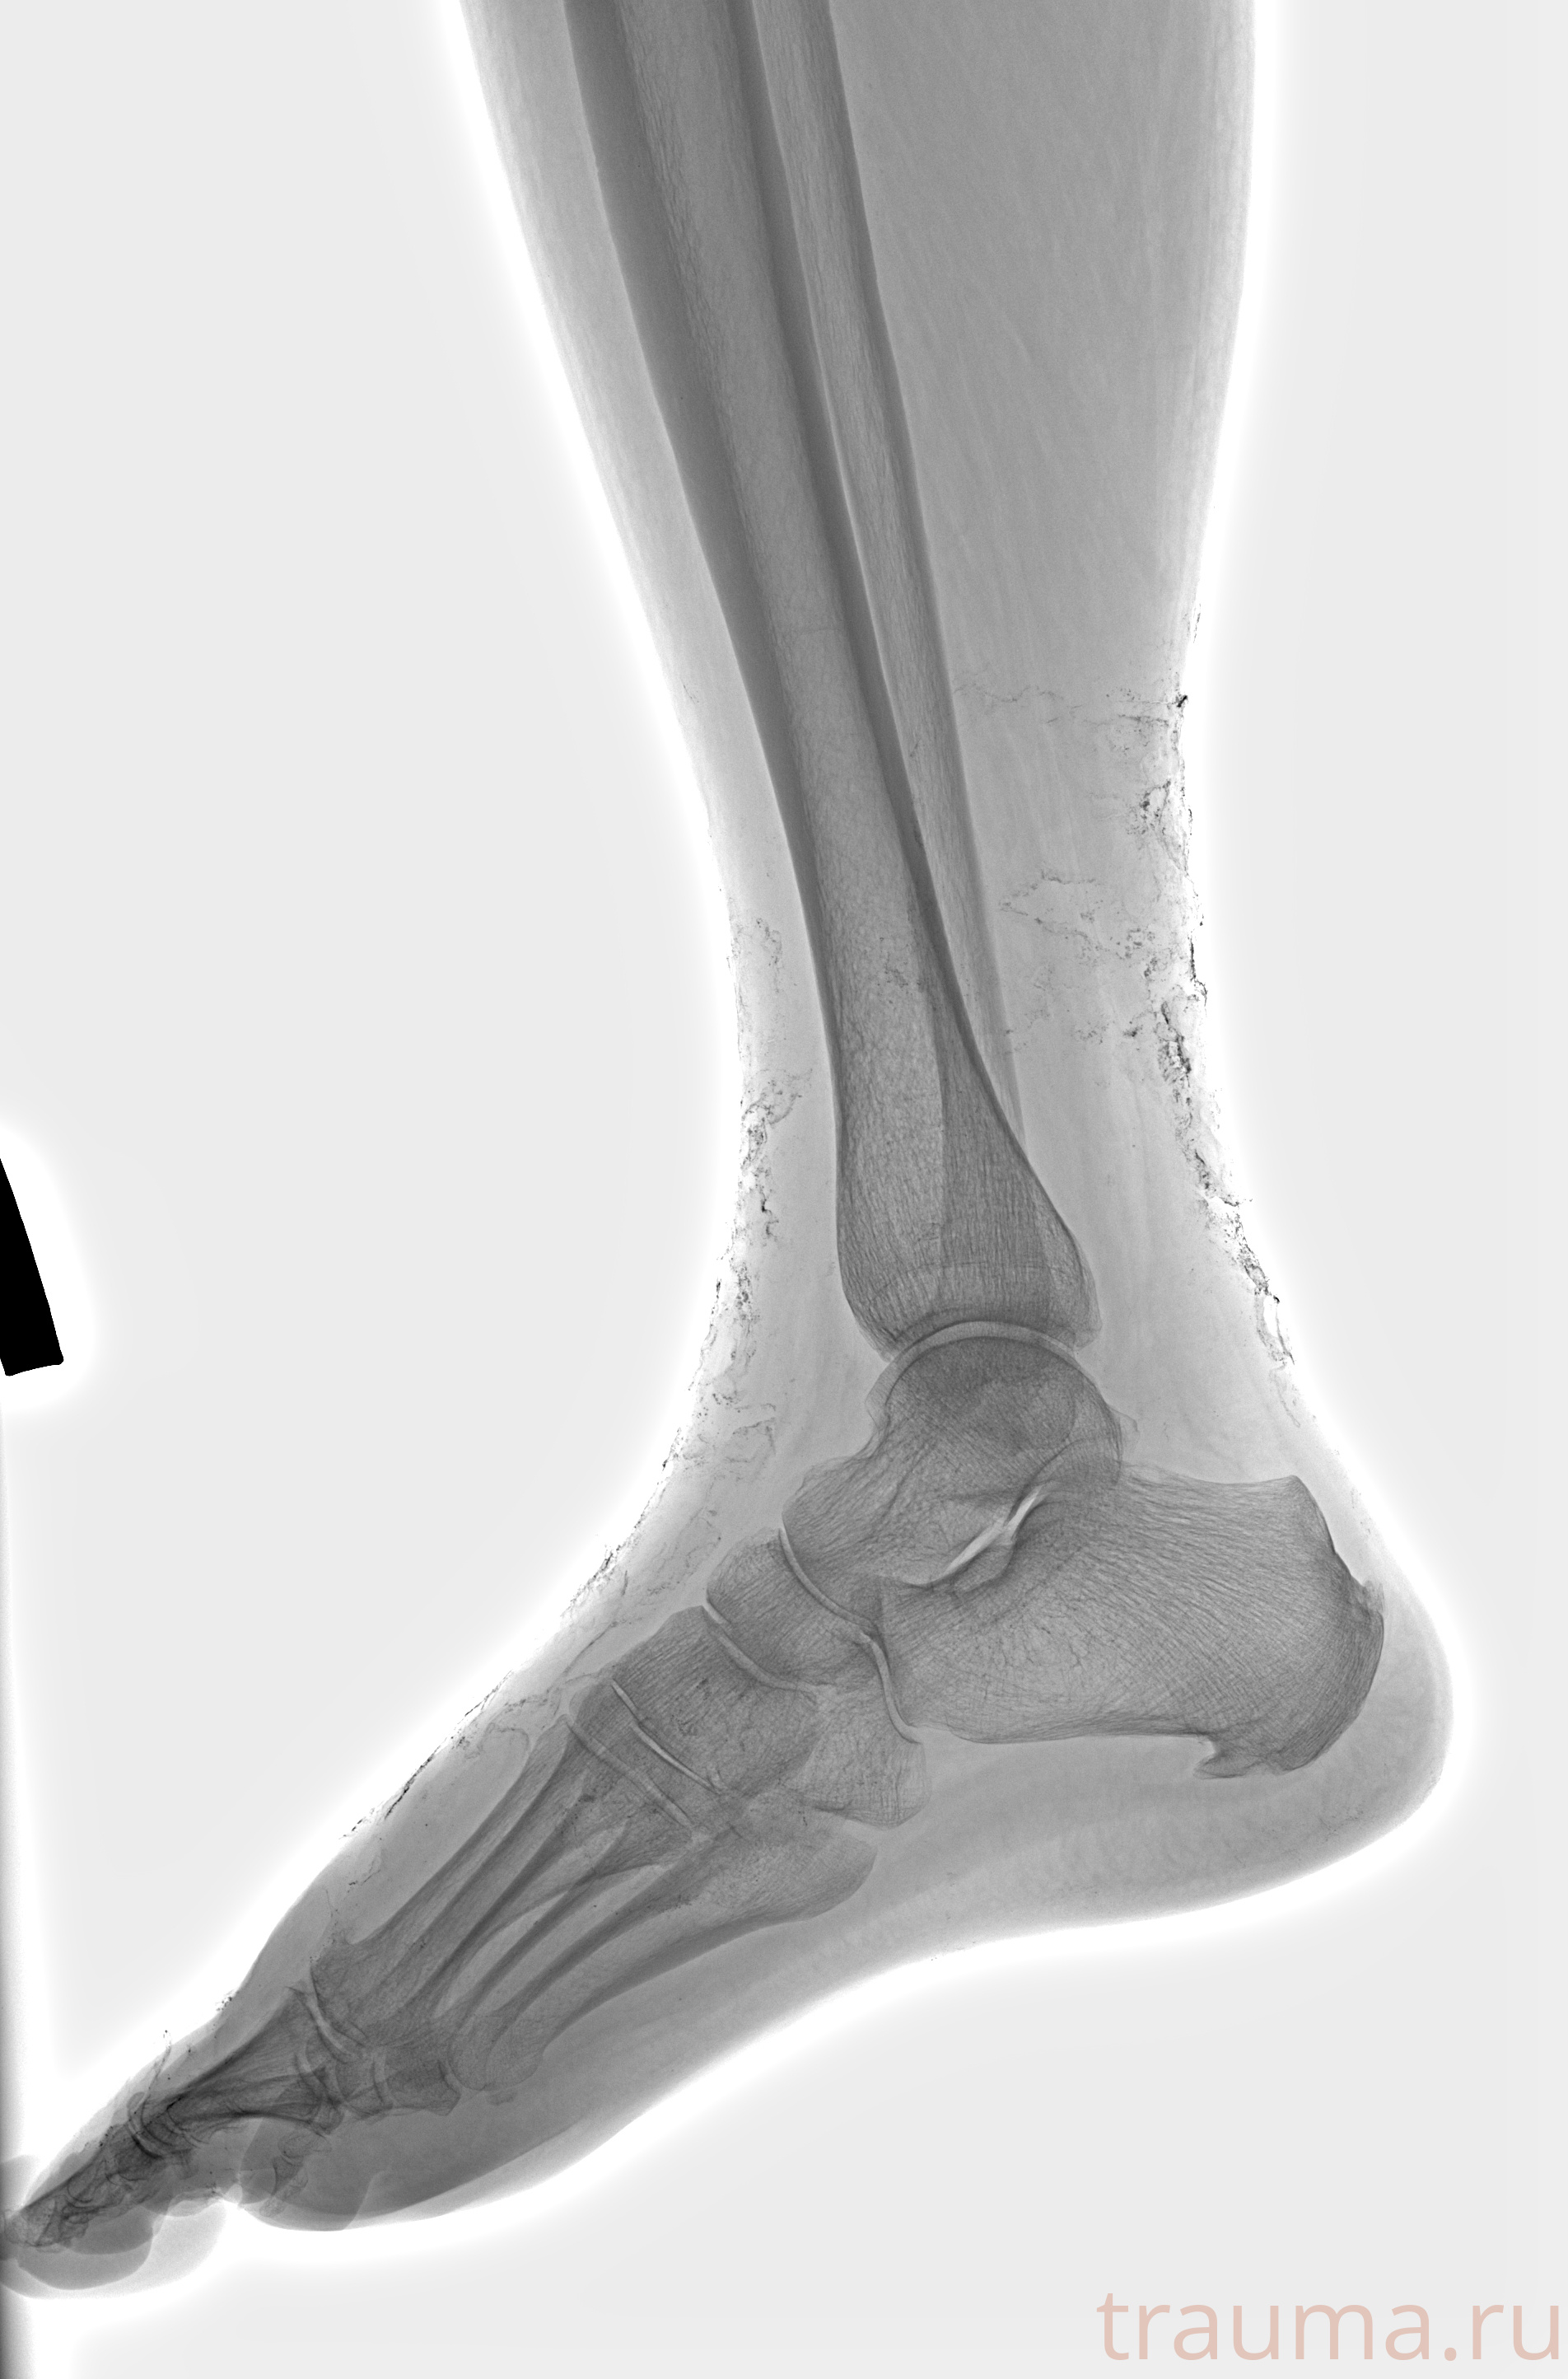

Рентген на дому: по вашему адресу приезжает врач-рентгенолог, травматолог-ортопед с мобильным рентгеновским аппаратом, проводит диагностику травмы или заболевания, делает необходимые рентгенограммы, дает рекомендации по дальнейшему лечению. Получить качественные снимки в домашних условиях возможно благодаря уникальной методике, разработанной МосРентген Центром для института  Склифосовского